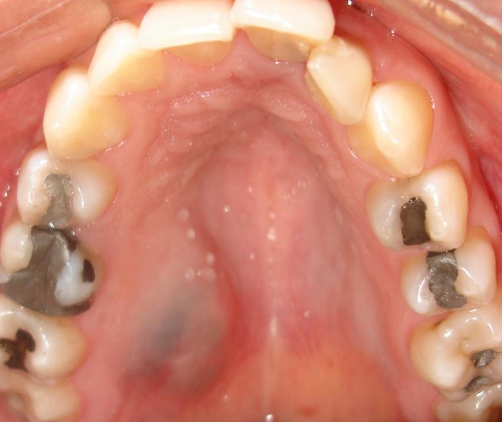

amalgam tattoo

macules or (rarely) as raised lesions which are blue, black, or gray in color, ill defined